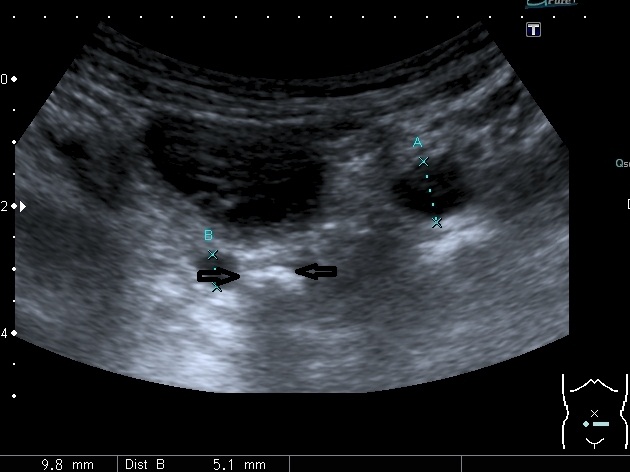

Если честно, и я изначально не совсем понял, где находится конкремент (а это конечно же конкремент), локализованный на урограммах. При первичном исследовании на УЗИ его я не видел (либо он спрятался за тенью конкремента мочевого пузыря, либо я обрадовался редкой находке конкремента такого размера в мочевом пузыре - 2.5 см, и не посмотрел что ниже). Тем не менее при ретроспективном анализе архивированных сонограмм, как мне кажется, он попал в один из сканов, м.б. не совсем чётко.

I20111114160229796.jpg

И всё -же, где конкремент :?:

Возможно, в дивертикуле либо в нижней трети мочеточника..

Верификация:

Выдержка из протокола операции- "...вскрыт мочевой пузырь, обнаружен камень 4 х 3х 2.5 см, плотный, удалён. При дальнейшей ревизии мочевого пузыря обнаружен вколоченный камень в шейке мочевого пузыря и в уретре, удалён камень 2 х 1.5 х 1.5 см. При осмотре устья левого мочеточника - последний зияет, мочеточник расширен до 1 см, учитывая расширение мочеточника, проведена антирефлюксная пластика по Грегуару..."